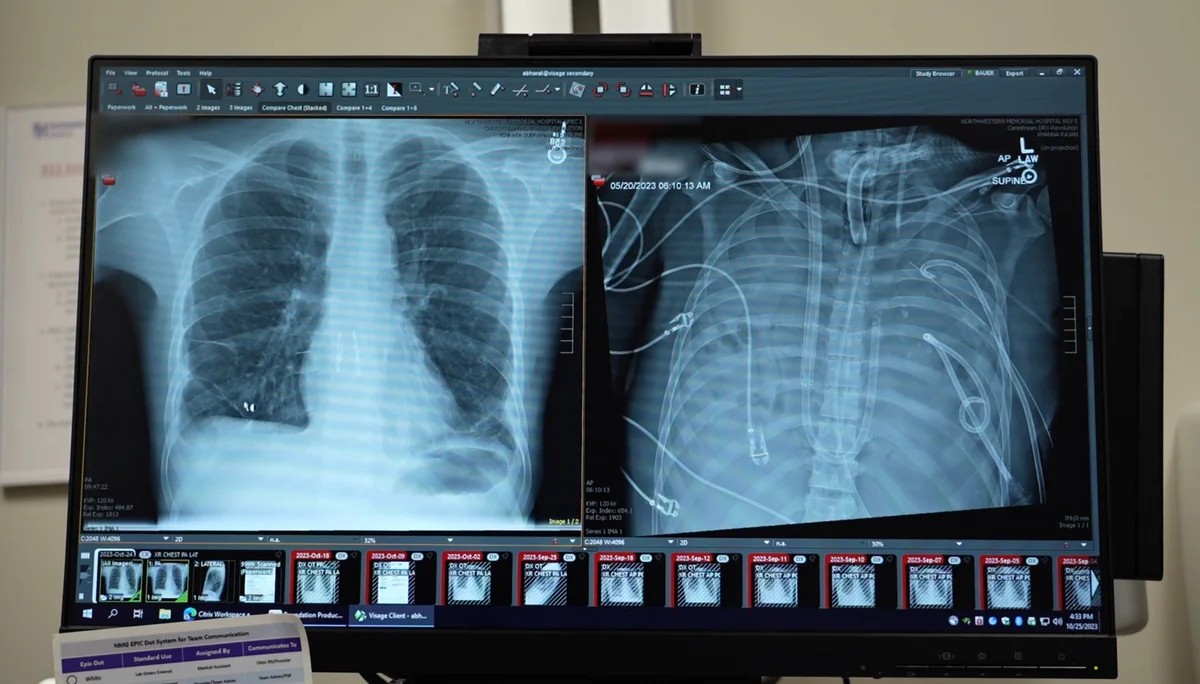

Торакальний хірург Північно-західного меморіального госпіталю Анкіт Бхарат згадує випадок 2023 року, коли 33-річний хворий на грип був на межі смерті через важку інфекцію Pseudomonas. Стан чоловіка стрімко погіршувався: у нього відмовляли нирки, серце ледь працювало, а легені були наповнені рідиною та гноєм. Після зупинки серця лікарі зіткнулися з критичним випробуванням: пацієнт потребував подвійної трансплантації легенів, але був занадто слабкий для процедури.

Стандартна підтримка життєдіяльності, екстракорпоральна мембранна оксигенація (ECMO), потребує функціонуючих легенів для ефективного функціонування. Без них система не може належним чином насичувати кров киснем. Бхарат і його команда розробили експериментальне рішення – систему “штучних легенів”, призначену для обходу органів пацієнта, які відмовляють. Ця система, по суті, служила мостом, перекачуючи кров з правого боку серця, щоб наситити її киснем і доставити до решти тіла.